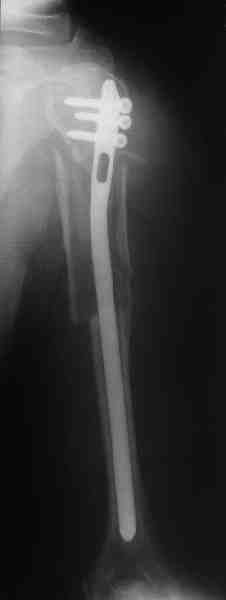

Прооперировали больную с переломом плеча все же гвоздем, Фото в приложении.

Отправитель: Никита Заднепровский 20 Август 2006, 22:38

Интересно, а канал рассверливали?

Гвоздик похоже ЦИТОвский?

Полагаю, бабушку можно поздравить с обретением

независимости. Судя по снимкам, неврологических расстройств нет и такая пациентка выпишется после снятия швов.

Какие рекомендации Вы дадите этой женщине на ближайшие 6 месяцев?

> Интересно, а канал рассверливали?

минимально

> Гвоздик похоже ЦИТОвский?

точно

Немножко уточню ответы Максима.

НЗ> Интересно, а канал рассверливали?

Только сформировали канал в головке. Диафиз не рассверливали. Хотя при необходимости, конечно, рассверлили бы.

НЗ> Гвоздик похоже ЦИТОвский?

Гвоздь большеберцовый нашей модификации, действительно, их делает предпричятие "ЦИТО". Тут взят 9 мм, укорочен до 240 мм, сделано дополнительное отверстие самое проксимальное, ну и для дистального винта.

НЗ> независимости. Судя по снимкам, неврологических расстройств

НЗ> нет и такая пациентка выпишется после снятия швов.

Неврологии нет, а выписать можно хоть на второй день, швы можно снять и в местной больнице.

НЗ> Какие рекомендации Вы дадите этой женщине на ближайшие 6 месяцев?

Почему так надолго? На ближэайшие недели - разработка движений, и все. Полагаю, что недель после 4 никаких рекомендаций не будет нужно, просто жить обычной жизнью сельской пенсионерки.